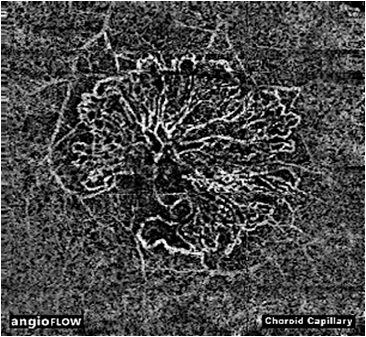

现在,有了“OCTA”这个新的检查设备,以上的问题都能很好的解决了,这项检查不但可以尽快明确诊断而且无创伤、非侵入、无痛苦、快捷方便。该设备不但可以清晰的显示视网膜、脉络膜毛细血管,而且可以具有OCT的功能同时清晰的显示视网膜各层的组织结构。该设备主要应用于视网膜血管疾病,脉络膜新生血管疾病,脉络膜肿瘤,糖尿病视网膜病变,脉络膜炎、青光眼及视神经血供的分析等的诊断和治疗效果的观察。

Angio OCT是一种非侵入性、无染料的快速分层观察眼底微循环毛细血管血流的新技术,由美国光视OPTOVUE唯一实现临床化并独家发布;能以无创的操作方式观察视盘、黄斑,甚至是脉络膜的血管形态。对于眼底病和青光眼的定性和定位诊断有着超越以往所有造影检查的安全性和准确性,具有很高的检查效率。

ANGIO OCT清楚显示 CNV: